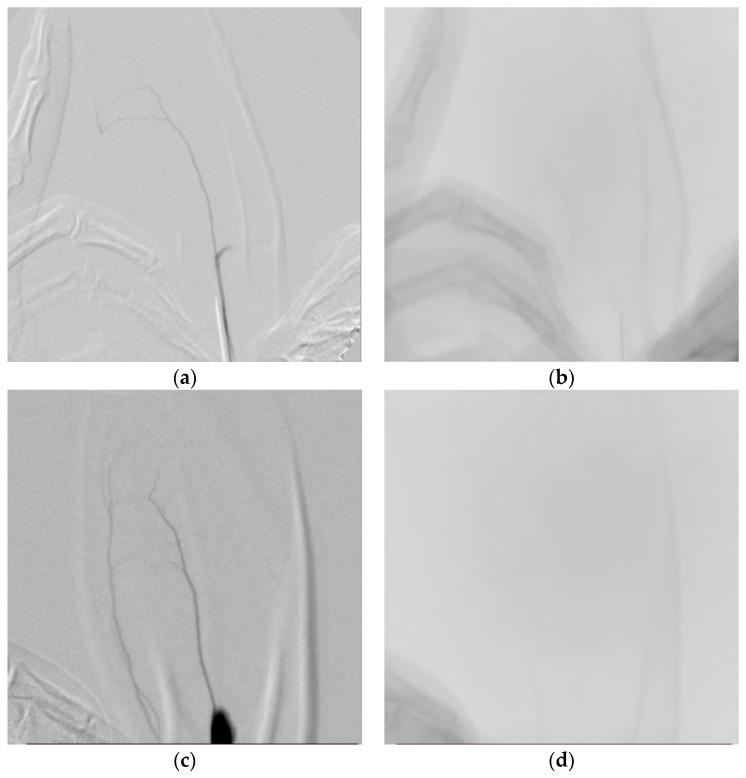

: This study aimed to develop an embolic agent with short-term embolic effects using cilastatin as the basic material. : The particle size distribution of 25 mg cilastatin-based short-term embolic agents was evaluated microscopically under three different mixing conditions. A total of thirty-six healthy male Sprague Dawley rats were divided into four groups. Each group of six rats was injected once into the tail artery with 0.4 mL each of (A) Cilastatin + D-Mannitol Mixture, (B) Iohexol, (C) Prepenem, and (D) embolization promoter (EGgel). : A visual inspection of the tail appearance of rats in each group was performed at 0, 3, 7, 15, and 21 days. At weeks 1 and 3, three rats per group were euthanized, and histopathological analyses were performed on the specimens obtained from each group. No significant differences were observed on day 7, but mild inflammation was observed in Group (D) on day 15. Histopathological inflammation scoring of tail central artery embolization was performed using a six-point scale (from 0 = absent to 5 = marked inflammation). Three groups were formed consisting of six male New Zealand white rabbits each: control, positive control, and test groups. The control group received an Iohexol injection (rabbits: 0.8 mL). The positive control and experimental groups were injected with prepenem and cilastatin/D-mannitol compound, respectively (0.8 mL), and vascular angiography was performed. The order of occlusion progression after embolization was as follows: test group, positive control group, and control group. : We developed a cilastatin/D-mannitol compound that exhibits characteristics of short-term embolization by utilizing the pharmacokinetic properties of cilastatin and the crystalline material D-mannitol. We evaluated its particle size distribution microscopically, conducted histopathological evaluation including inflammation via animal experiments, and assessed the embolization effect.

本研究旨在以克拉维酸钾为基础材料,开发具有短期栓塞效果的栓塞剂。采用显微镜观察了三种不同混合条件下 25mg 克拉维酸钾基短期栓塞剂的粒径分布。将 36 只健康雄性 Sprague Dawley 大鼠随机分为 4 组,每组 6 只大鼠,分别经尾动脉注入 0.4mL 的(A)克拉维酸钾+甘露醇混合物、(B)碘海醇、(C)比阿培南和(D)栓塞促进剂(EGgel)。观察各组大鼠尾外观,于 0、3、7、15 和 21 天进行视觉评估。在第 1 周和第 3 周,每组处死 3 只大鼠,对每组获得的标本进行组织病理学分析。第 7 天未见明显差异,但第 15 天 D 组可见轻度炎症。采用 6 分制(0=无,5=明显炎症)对尾中央动脉栓塞的组织病理学炎症评分进行评估。每组 6 只雄性新西兰白兔分为三组:对照组、阳性对照组和实验组。对照组注射碘海醇(兔:0.8mL),阳性对照组和实验组分别注射比阿培南和克拉维酸钾/甘露醇复合物(0.8mL),并进行血管造影。栓塞后闭塞进展的顺序如下:实验组、阳性对照组和对照组。我们利用克拉维酸钾的药代动力学特性和结晶性物质甘露醇,开发了一种具有短期栓塞特性的克拉维酸钾/甘露醇复合物。我们通过显微镜观察评估了其粒径分布,通过动物实验进行了包括炎症在内的组织病理学评估,并评估了栓塞效果。